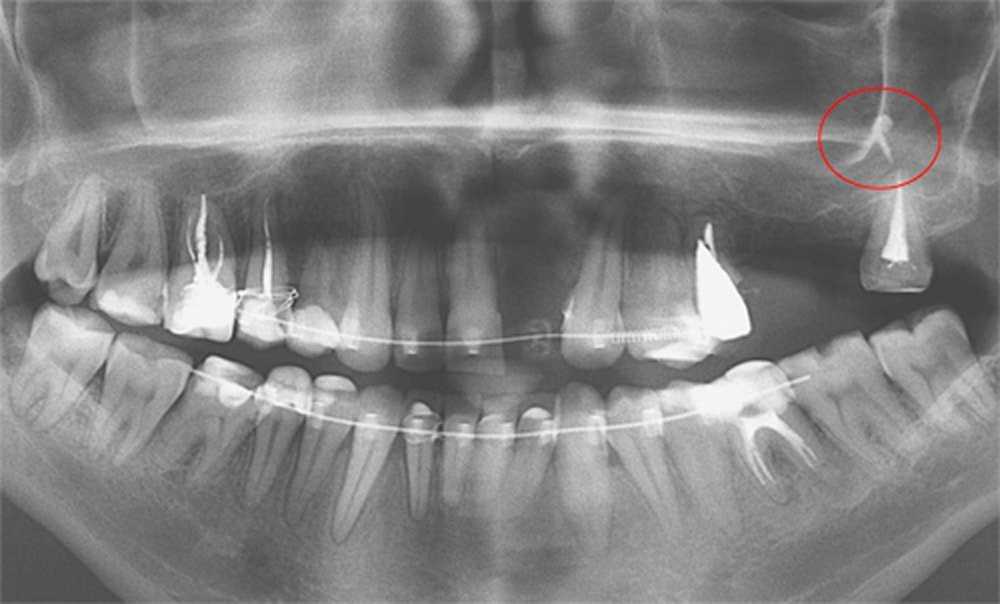

Обратитесь к стоматологу для рентгеновского снимка, чтобы определить точное расположение излишков пломбировочного материала.

Выведение материала при пломбировании корневых каналов в носовую пазуху.

Почему гуттаперча выходит за верхушку? Часть 1

Осложнения при лечении корня зуба

Осложнения при лечении пульпита. Попадание пломбировочного материала за пределы корня зуба

Какой силер лучше? Выход силера за верхушку. Силер в стоматологии

Пломбировочный материал в Гайморовой пазухе и что с этим делать. В конце готовлю плов ))))